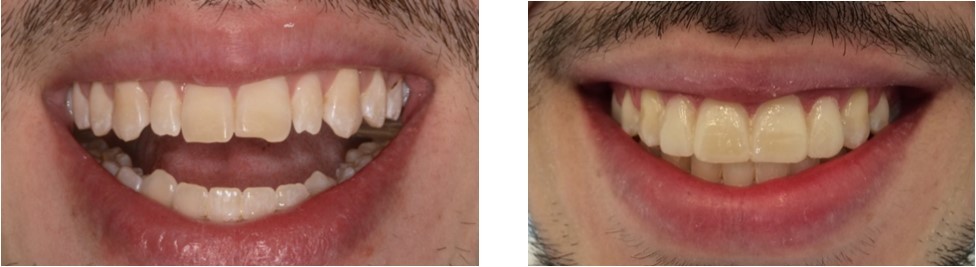

After the ending of the orthodontic treatment, the patient remained dissatisfied with the appearance of the maxillary incisors, no longer in relation to the positioning of the teeth, but in relation to the color and shape [Figure 3]. The smile esthetic was planned in detail with Digital Smile Design (DSD), through photographs and study models. The working cast was waxed up and a silicon template was used to transfer the waxing of the incisors. With the aid of the silicon template, a Mockup with bisacrylic resin (2 Structur-Voco-Cuxhaven, Germany) was obtained for the approval of the planning by the patient [Figure 3b].

Figure 3.(a) Orthodontic treatment ending (b) Mockup